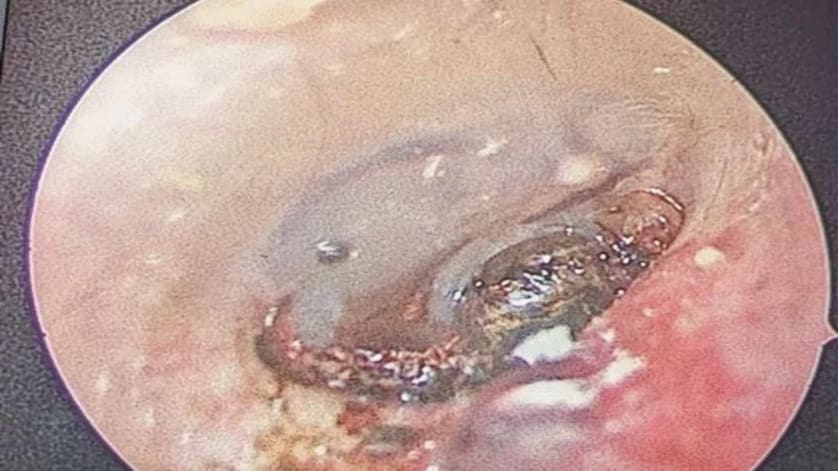

January 16, 2025 Vertigo, Emesis, Auditory Impairment: What's Your Diagnosis? A patient presents with sudden-onset right-sided otalgia accompanied by vertigo, emesis, and auditory impairment. Your otoscope reveals an unexpected finding. What's your diagnosis? Conexiant